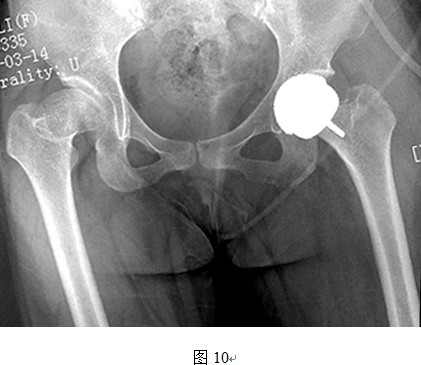

(1)头和臼假体之间有时很难良好匹配

图中所示,按照股骨侧决定假体大小原则,匹配的髋臼假体较原始臼来说过小,髋臼磨挫不充分,假体与髋臼匹配不良。